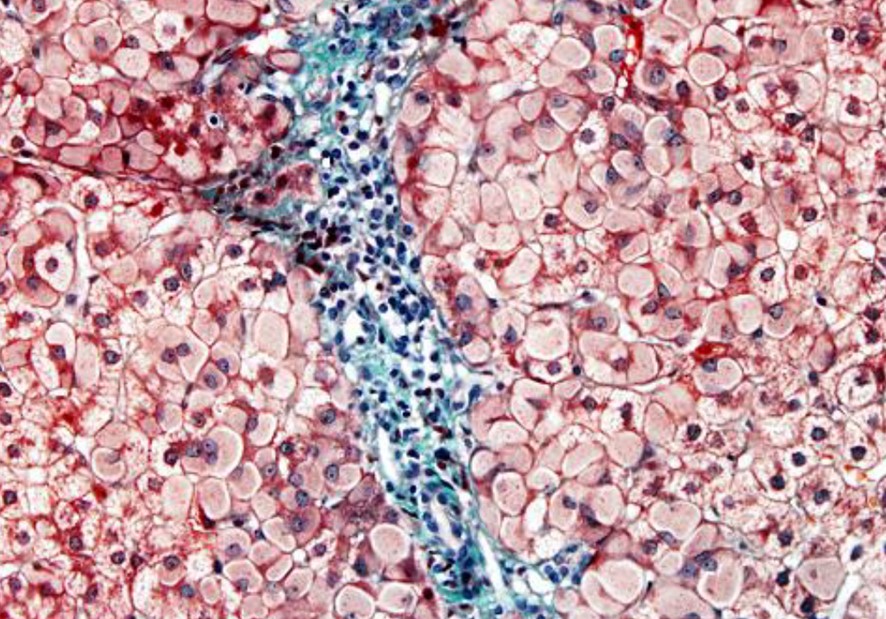

Jo penso que Hadziyannis, quan va tornar a Atenes del congrés, devia revisar les biòpsies hepàtiques que tenia de portadors de VHB sense lesió hepàtica i va veure els hepatòcits esmerilats que li havien passat per alt. Porta aquestes biòpsies al laboratori de Popper a Nova York, el qual demostra que els hepatòcits esmerilats es tenyien amb l’orceïna i contenien HBsAg en excés (Fig.2).

Quan ja havien passat uns anys d’aquesta història, vaig veure diverses biòpsies hepàtiques que tenien hepatòcits esmerilats una mica diferents dels que estaven infectats per VHB. Se situaven en les àrees periportals, deixaven un halo clar entre el cos d’inclusió i la membrana cel·lular, i no es tenyien amb l’orceïna, però sí amb el PAS (Fig.3). Vaig anar a buscar informació a la història clínica, i tots els malalts que tenien aquest tipus de cèl·lules eren alcohòlics en tractament amb cianamida, que és un fàrmac aversiu de l’alcohol. Vaig publicar aquestes observacions que ampliaven les etiologies dels hepatòcits esmerilats (M Bruguera, C Lamar, M Bernet, J Rodés. Hepatic disease associated with ground-glass inclusions in hepatocytes after cyanamide therapy. Arch Pathol Lab Med., 1986 ;110(10):906-10; Bruguera M, Parés A, Heredia D, Rodés J. Cyanamide hepatotoxicity. Incidence and clinico-pathological features. Liver. 1987 Aug;7(4):216-22)